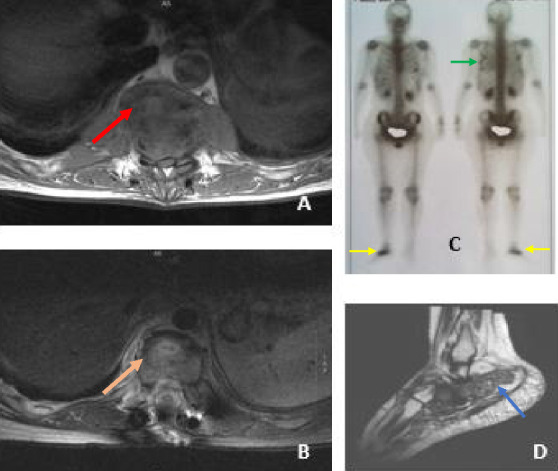

Introduction: Tuberculosis (TB) of bones and joints is a relatively rare manifestation of the disease. Biopsy is the key to diagnosing it, while chemotherapy is the cornerstone of treatment. Some patients need surgery in addition to anti-TB drugs. We present a series of eight cases of bone and joint TB. Method: The files of the patients with TB diagnosed and treated at the Pulmonary Department of Aristotle University of Thessaloniki (A.U.Th.) between 2013 and 2022 were reviewed. Patients with a bone or joint infection due to M. tuberculosis were selected. Cases Presentation: During these ten years, 307 cases of TB were found. Eight of them were TB of bones and joints (2.6%). Six patients were men and two women, with a mean age of 53.5 years and a standard deviation of 18.2 years. Half of them were native Greeks. The spine was involved in 4 cases, while two of the patients also had pulmonary TB. In seven cases, M. tuberculosis DNA was detected by PCR. Chemotherapy with anti-TB drugs was administered to all eight patients, with three of them undergoing surgery in addition to anti-TB medication. The minimum treatment duration was twelve months. Six out of eight cases had a good outcome. Conclusions: TB is a rare cause of infection of bones and joints; however, it should be included in the differential diagnosis of bone lesions. PCR for M. tuberculosis seems to have significantly good results in microbiological confirmation of osteoarticular TB.